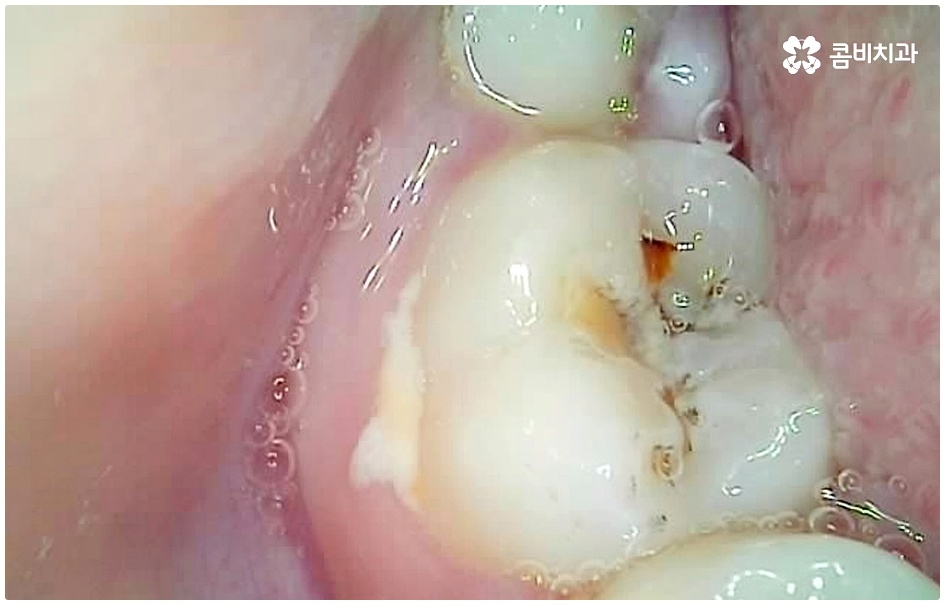

이 때 교합면, 즉 치아의 씹는 면이 아닌 치아 사이 충치가 생겼다면 쉽게 발견하기도 어렵고 치료를 위한 접근 역시 까다롭기 때문에 주의하실 필요가 있습니다. 물론 가장 흔하게 발생하는 것은 넓고 홈이 파여 있으며 직접 음식물을 저작하는 교합면에 생기는 충치일 것이나 음식물 찌꺼기가 끼기 쉽고 세균이 서식하기도 쉬우며 양치질을 하더라도 칫솔모가 잘 닿지 않기 때문에 관리가 어려운 치아 사이 좁은 틈새에도 역시 충치가 잘 생길 수 있는 거예요.

치아 사이 충치는 치아끼리 맞닿아 있는 부분이라 노출이 잘 되지 않기 때문에 육안으로 식별이 어려운 경우가 많은데, 만약 눈으로 확인될 정도라면 질환이 이미 많이 진행한 상태이므로 명동치과 에서 빠른 치료를 받아주실 필요가 있어요.

치아의 구조를 살펴보면 겉표면인 단단한 법랑질은 교합면에서 가장 두껍고 잇몸쪽으로 갈수록 얇아지기 때문에 치아 사이의 인접면은 치아의 신경과 한층 가까워서 충치가 조금만 진행되어도 신경치료를 받아야 할 수 있으며 인접면 충치가 심하여 레진이나 인레이 수복으로 치아의 외형을 재현하기 어려운 경우에는 치아 전체를 다듬어 씌우는 명동치과 크라운 치료를 해줘야 하니 부담이 커지기 전에 치료 시기를 놓치지 않도록 주의하시는 게 좋을 거예요.

인접면 충치는 일반적으로 양치를 꼼꼼히 하기 어려운 아동에게 많이 발생하지만, 식습관이나 구강위생 관리 소홀 등을 이유로 성인에게도 빈번히 발생하는 질환이며 발견과 치료에 있어 일반적인 충치보다 어려움이 크기 때문에 주기적인 명동치과 검진 및 스케일링 처치, 그리고 치실 사용 등 꼼꼼한 양치질 등을 통해 초기 대처 및 예방을 해주는 것이 매우 중요하다고 할 수 있습니다.